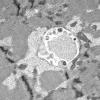

Pompe Disease (3)